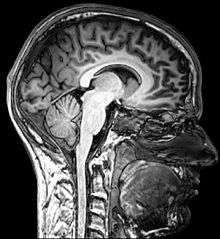

Behavioural Science

Behavioural Science, often referred to as Psychology is the study of the human mind. This includes the way people adapt, think, co operate, become motivated, and it forms individual personality traits. Psychology is plays an important role in the development of human activity involving social, cognitive and behavioural sections of the brain. To become a qualified psychologist it is required to have a Behavioural Science degree. To achieve this studying a bachelor of Behavioural Science or a bachelor of Psychology at a University.[53]